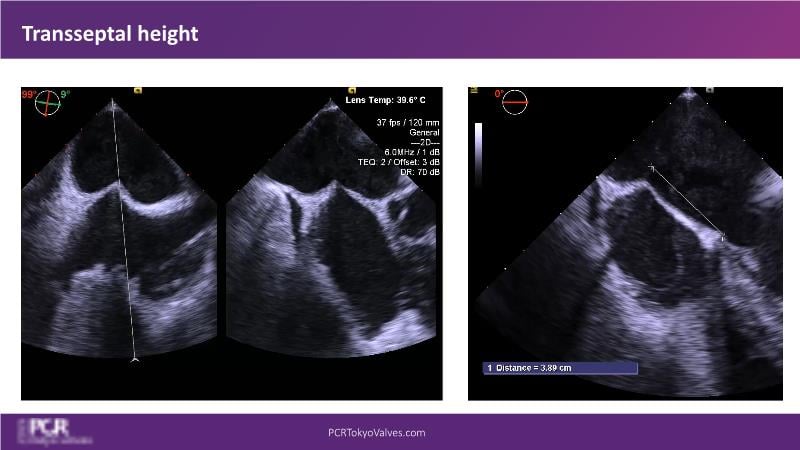

Watch this session to get an overview of a new TEER device, follow the step-by-step procedure related to initial experiences with this device for a Japanese patient with degenerative mitral regurgitation, learn about the latest data from RCT and registries, and follow discussions of challenging TEER cases!

- To understand how novel TEER device provides new possibilities in TEER

- To learn procedural step-by-step of novel device